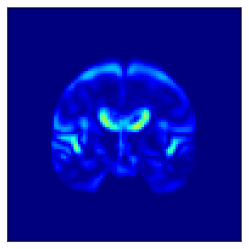

(a) (b) (c)

Figure 5: Brain regions affected by the one dimension with the largest difference between the AD and CN conditions among the low-dimensional representation obtained. (a) naïve β𝛽\beta-VAE, (b) β𝛽\beta-VAE (TW), and (c) Loc-VAE.

Fig. 5 shows the difference in the reconstructed images (the coronal, sagittal, transverse planes) with and without perturbation to one dimension of the low-dimensional representations that most affect the disease features between AD and CN. This one dimension is chosen to have the largest expected value of the difference in the mean vector (150150150 dim) between AD and CN.

In Fig. 5, the influence of dimensions that may contribute to the diagnosis of AD is examined, and it can be seen that the naïve β𝛽\beta-VAE captures not only the important areas around the ventricles shown in Fig. 2 but also the edges of the brain and other areas. Loc-VAE, however, is more limited and captures this region better. This result shows that Loc-VAE acquires a specific dimension of the disease features on low-dimensional representation. Disease feature–specific dimensions serve as materials for the neurologist to assess similar cases displayed by CBIR.